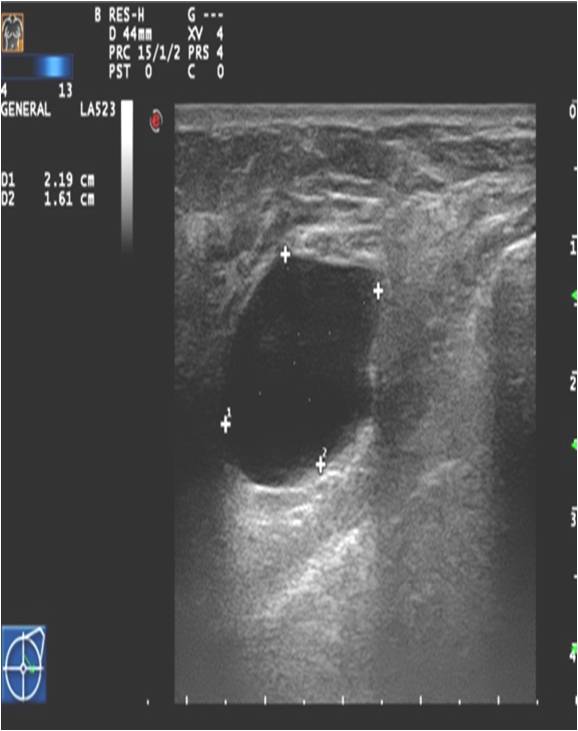

The soft-tissue lesions can appear as well-defined, rounded or oval shaped (Pictures 13.,14.) or as ill-defined, star-shaped masses (Picture 15.). Rounded or oval lesions are in most cases benign and their malignant proliferation is rare, they do not require surgical removal. These lesions are usually cysts and fibroadenomas, at other times hamartomas, lipomas and at very few times malignant tumors.

Ultrasonography can help in their differentiation; can depict anechoic cystic lesions (Picture17.) or solid masses (Picture 18.). These lesions usually each have a smooth, sharp edge and echo-enhancement can appear behind them. Rarely, cysts contain tumors. (Picture19.).